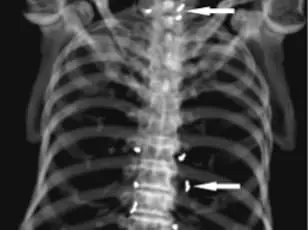

The patient, who had been undergoing gold thread acupuncture—a practice involving the insertion of sterile gold threads into the skin—was shocked to discover during an X-ray that hundreds of these threads had been left in her knees.

However, the presence of these threads in her knee, revealed by the X-ray, complicated her doctors’ ability to assess the true state of her joint damage.

The woman’s case, detailed in the New England Journal of Medicine, has drawn attention from the medical community.

Doctors treating her noted that the gold threads obscured critical anatomical details on scans, making it harder to diagnose her condition accurately.

X-rays revealed thousands of the embedded threads throughout his body, a testament to the long-term accumulation of these foreign objects.